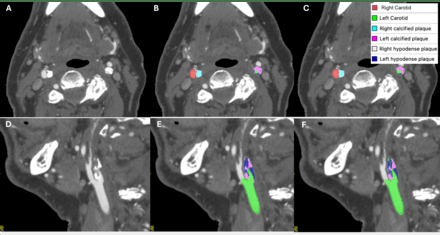

Results: 422 cases were used for training and 106 for testing. In testing data, the fully automated tool achieved excellent performance for bilateral segmentation of carotid lumens (Dice 0.91, 95%CI:0.90-0.92, e.g. Figure 1). For detection of calcific and hypodense plaque components, respectively, the model achieved sensitivity of 96.5% (95%CI:89.3-99.1%) and 97.3% (89.6-99.5%), specificity of 95.2% (74.1-99.8%) and 75.8% (57.4-88.3%), positive predictive value of 98.8% (92.6-99.9%) and 89.9% (80.5-95.2%), negative predictive value of 87.0% (65.3-96.6%) and 92.6% (74.2-98.7%), and accuracy of 96.2% (90.1-98.8%) and 90.6% (82.9-95.1%, e.g. Figure 2). Dice score was 0.73 (0.69-0.76) for calcific plaque and 0.53 (0.49-0.57) for hypodense plaque.